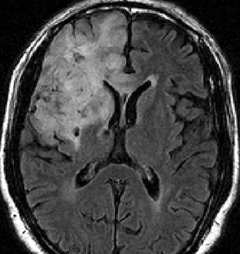

これは30歳くらいの若い女性にできた乏突起膠腫です。軽いけいれん発作を生じましたがその後は無症状です。上がT2強調画像で,下がガドリニウム増強像です。CTでは石灰化が散在していました。大脳深部をほとんど埋めるように腫瘍は浸潤して広がっています。脳外科の先生にこの患者さんが無症状だといっても信じてもらえないのですが本当です。

ほんの少しだけ腫瘍をとって(生検術)病理診断を確定しました。

腫瘍が大きすぎるので,認知機能を保つために,全脳照射30グレイとテモゾロマイド化学療法を2年しました。以来9年以上たちますが,とても頭の良い方でちゃんと働いておられます。

この患者さんから学ぶことはたくさんあります。この広範に伸展した腫瘍はおそらく10歳前後から存在したのだと想像されます。腫瘍が発見されず未治療だったからこそ,これまで通常の生活ができたのかもしれません。

また,グレード2の乏突起膠腫には限りなくグレード1に近い高分化型の腫瘍が存在するということです。乏突起膠腫は手術で完全摘出できれば治るのでしょうが,手術によって認知機能障害や高次脳機能障害を生じれば社会生活を一人ですることは難しくなります。分化型の乏突起膠腫は,正常の神経細胞や脳機能を破壊しないで浸潤増大しますから,脳の中にこんなに広がっても,何の症状も出さないということがあります。同じグリオーマでも膠芽腫などと比べれば大きな差があるのです。治療後の生存の質を考える時に,このような例があるということを思い出すことは大切です。